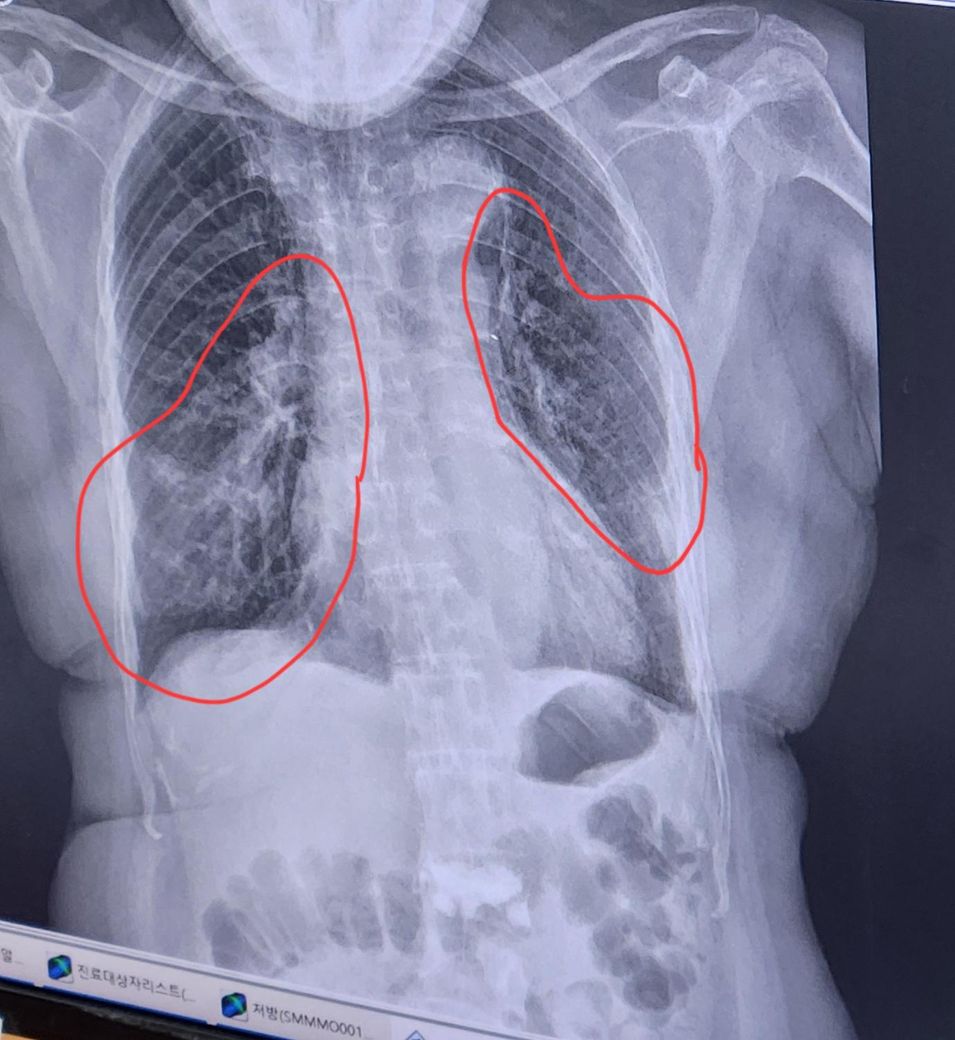

동그라미 친 부분이 다 염증인가요?

심한편인지요?

현재 발열없음/기침가래콧물있음

가래색 연노랑/산소포화도 96입니다.

엑스레이 이미지를 살펴보면, 동그라미 친 부분에서 폐의 양쪽 하부에 걸쳐 불투명한 음영이 관찰됩니다. 이 음영은 일반적으로 폐렴에서 나타나는 염증 소견으로 보여요. 특히, 폐렴은 폐의 공기주머니(폐포)에 염증이 생겨 엑스레이에서 이런 흐릿한 패턴을 보이게 합니다. 따라서 동그라미 친 부분이 대부분 염증으로 인한 소견일 가능성이 높습니다. 다만, 정확한 진단은 영상의학과나 호흡기 내과 담당의가 환자의 임상 증상과 다른 검사 결과를 종합하여 판단해야 합니다.

염증의 정도는 엑스레이상으로 양쪽 폐 하부에 걸쳐 비교적 넓게 퍼져 있는 것으로 보아 경미한 수준은 아닌 것 같습니다. 하지만 현재 발열이 없고 산소포화도가 96%로 안정적이며, 가래 색깔이 연노란색인 점을 고려하면 심각한 중증 폐렴으로 진행되지는 않은 상태로 보입니다.

기침, 가래, 콧물 등의 증상이 있지만, 산소포화도가 정상 범위에 있고 발열이 없는 점은 긍정적인 신호죠

다만 고혈압이 기저질환으로 있는 60세 여성 환자이므로, 폐렴이 악화되지 않도록 항생제 치료와 함께 충분한 휴식, 수분 섭취, 그리고 주치의의 지시에 따라 경과를 잘 관찰하는 것이 중요합니다. 추가적인 염증 진행 여부를 확인하기 위해 필요하다면 후속 엑스레이 촬영이나 혈액검사(CRP, 백혈구 수치)를 고려해볼 수 있습니다.